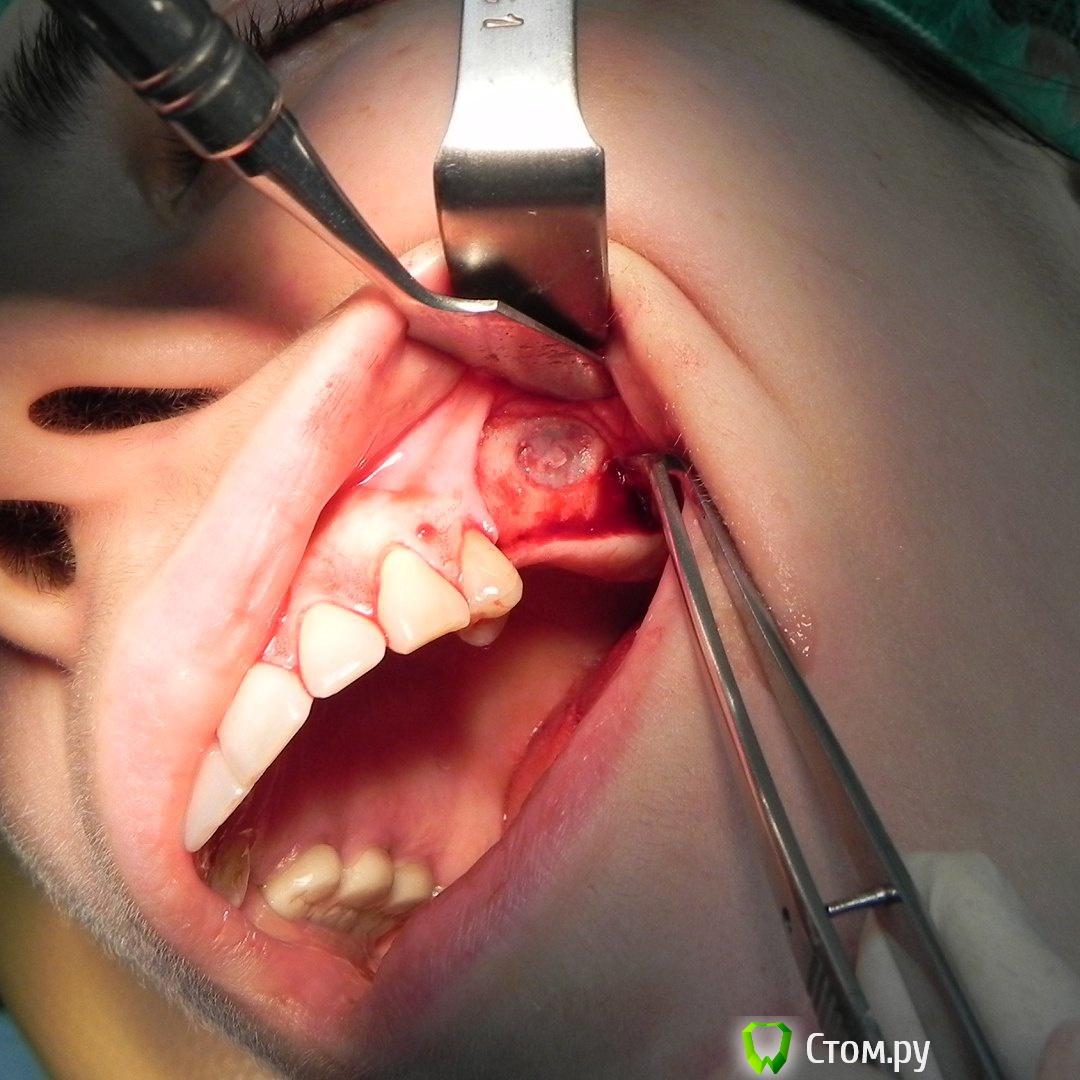

Kostoprav Опубликовано 30 мая, 2015 Автор Поделиться Опубликовано 30 мая, 2015 все работает, чистая синтетика без ауто! это не единичный случай. 2 Ссылка на комментарий

Kostoprav Опубликовано 31 мая, 2015 Автор Поделиться Опубликовано 31 мая, 2015 а что за система имплантатов? noris Израиль Ссылка на комментарий